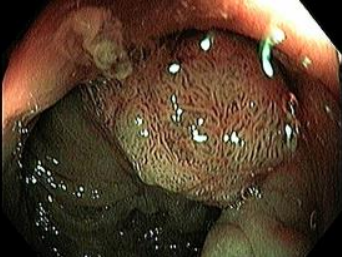

Tratamiento del Sobrepeso

BALON GASTRICO

GASTROPLASTIA ENDOSCOPICA